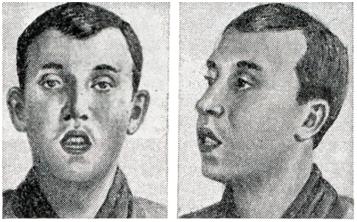

Изменение формы лица и верхней челюсти, постоянно открытый рот, вялое и безразличное выражение (рис. 4) получило название аденоидного лица, или внешнего аденоидизма (habitus adenoidicus, facies adenoidica).